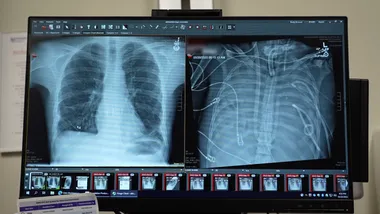

У 2023 році медики вперше успішно застосували систему штучних легень для підтримки життя пацієнта після видалення його власних органів. 33-річний чоловік зі Сент-Луїса потрапив до лікарні з грипом типу B, після чого його стан різко погіршився через вторинну інфекцію бактеріями Pseudomonas aeruginosa, стійкими до антибіотиків.

Інфекція поширилася на кров, а подвійне ураження разом із надмірною імунною реакцією організму призвели до повної відмови легень. Молекулярні тести показали, що органи не відновляться. За словами Анкіта Бхарата, керівника відділення торакальної хірургії Медичної школи Файнберга Північно-Західного університету в Чикаго, пацієнт активно помирав і не міг отримати трансплантат через активну бактеріальну інфекцію.

Хірурги прийняли рішення видалити уражені легені та підключити чоловіка до розробленої ними системи штучних легень. Пристрій забирає кров з правої частини серця, пропускає її через помпу для насичення киснем та видалення вуглекислого газу, після чого направляє до лівої частини серця для подальшого перекачування по тілу. Така система не лише забезпечує оксигенацію, а й підтримує нормальну роботу серця.